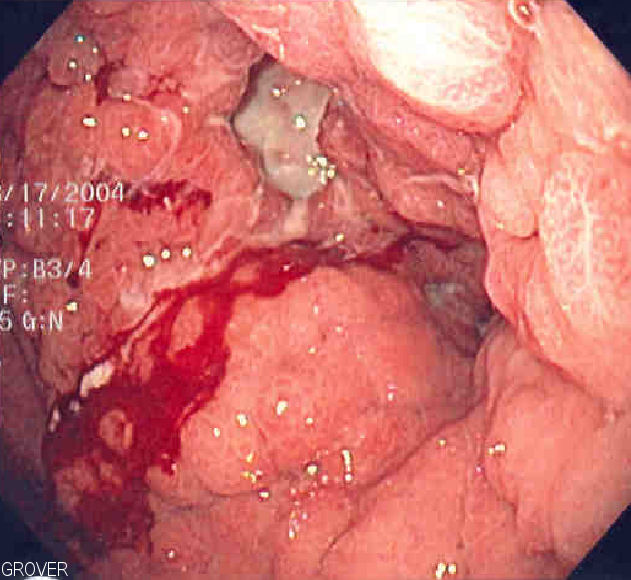

- 위장관

- * 상부 위장관 출혈

- * 하부 위장관 출혈

- * 잠혈 위장관 출혈

위장관 출혈은 상부 위장관 출혈, 하부 위장관 출혈, 잠혈 위장관 출혈로 나뉜다. 요로에서는 혈뇨(요로 출혈로 인한 소변 내 혈액)가 발생할 수 있다.